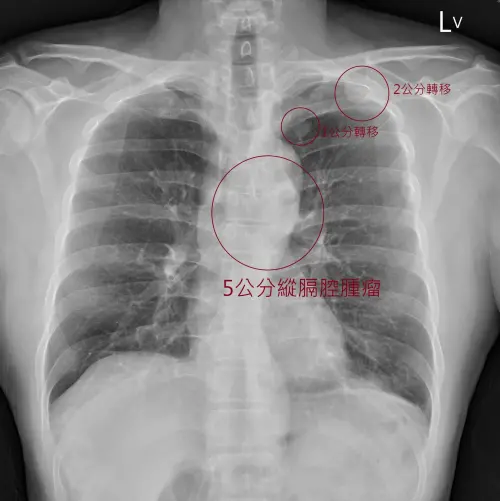

蘇一峰先在文中放上X光圖,讓網友看看腫瘤,並在留言處附上圈起的腫瘤示意圖「躲在主動脈裡面,五公分縱膈腔腫瘤」,讓網友也紛紛回應「好可怕,跟空污有絕對關係」、「好可怕的無症狀」、「癌症讓人難受的是人生突然被畫下句點」。

▲一名4旬男沒有任何不舒服,健檢去年正常、今年卻發現已癌末。(圖/翻攝自蘇一峰臉書粉專)